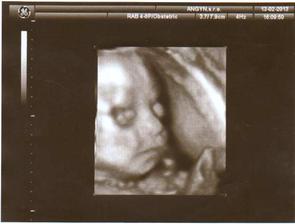

3.4.2013 - 31tt. návšteva poradne, USG, 1779 gramov, 3D úspešné, smiala sa a vyplazovala jazyk